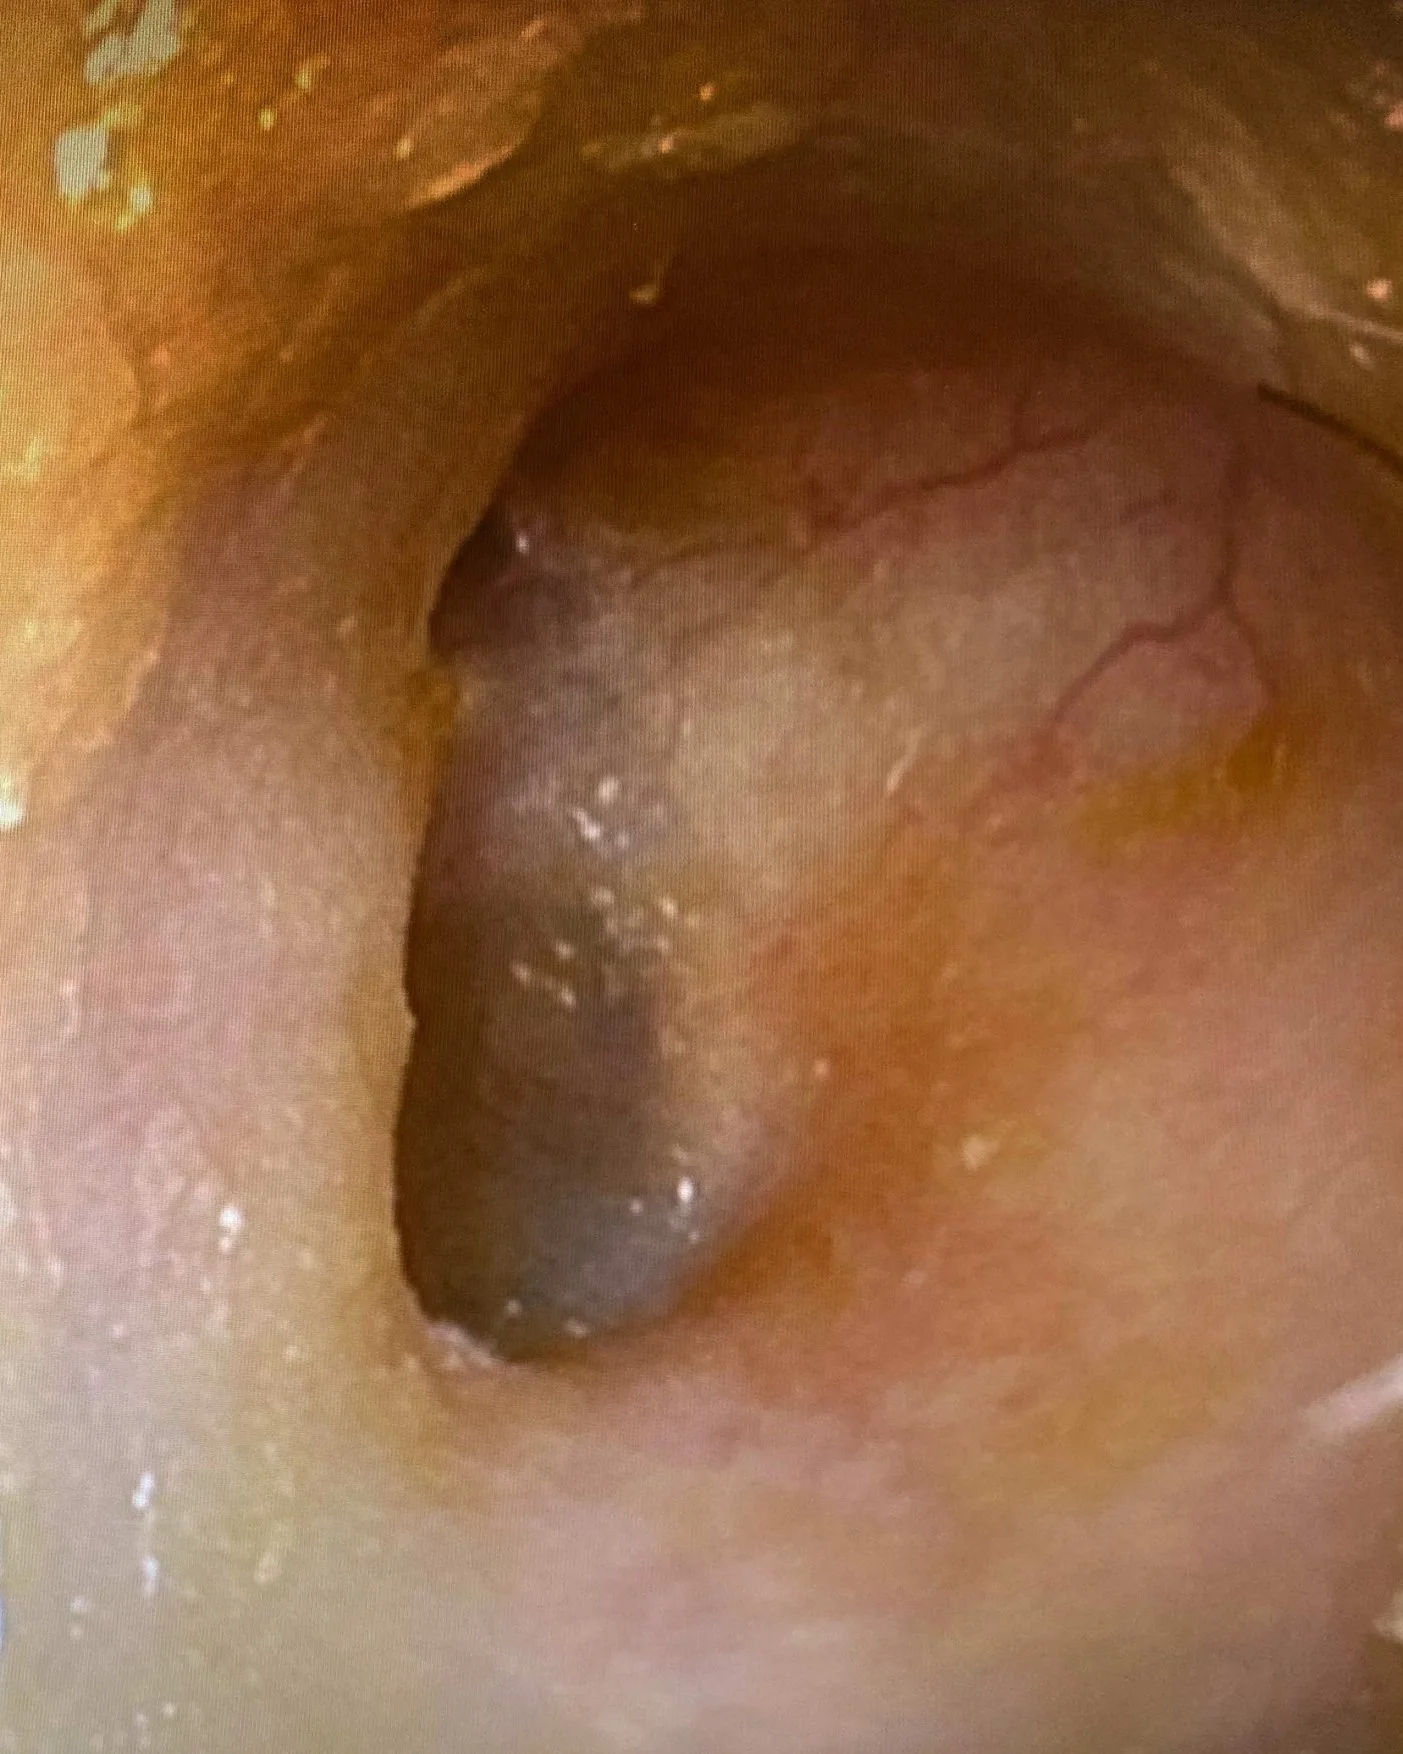

The current seven-day course of drops often fails. In comparison, ENT401 is a single dose treatment for otitis externa of bacterial or fungal origin, administered by a health care provider with relief of symptoms within 2-3 days and less than 1% persistent disease.

AFTER TREATMENT (7 DAYS)